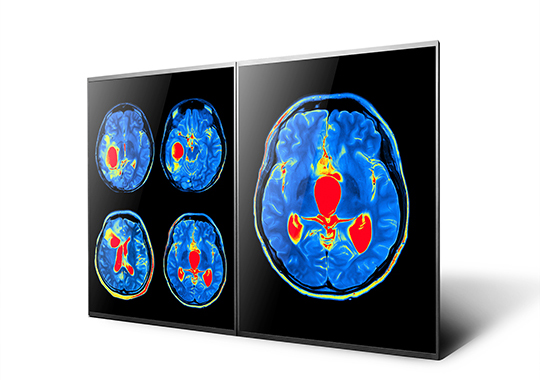

AUO general displays continue to lead the industry through years of research and development. In addition to the usual image clarity, AUO’s displays boast high reliability with high brightness, resistance to wide temperature ranges, and shock-resistant designs, allowing for long periods of stable usage even under bright light or harsh environments. Features such as high-resolution, high-contrast, and wide color gamut are suitable for applications such as medical-grade panels in achieving an accurate diagnosis.

Professional medical-grade display technology

Solutions with high-resolution, wide color gamut, and ultra-high contrast ratio provide clear images to identify minute differences in human tissue and blood. 3D display technology offers vertical 3D images with wide viewing angles in high resolution and vivid colors. Advanced reflectionless technology (A.R.T.) eliminates the impact of environmental light sources to present digital pathological images in true color and consistent features.